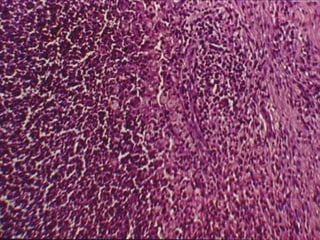

MENINGITIS BACTERIANA Anatomía Patológica: Hallazgos microscópicos: Microhemorragias en Aracnoides y Piamadre. Proliferación de microglia. Destrucción de células ependimarias. Infiltración de P.M.N. EDEMA.

MENINGITIS BACTERIANA AnatomíaPatológica: Hallazgos microscópicos: Microhemorragias en Aracnoides y Piamadre. Proliferación de microglia. Destrucción de células ependimarias. Infiltración de P.M.N. EDEMA.